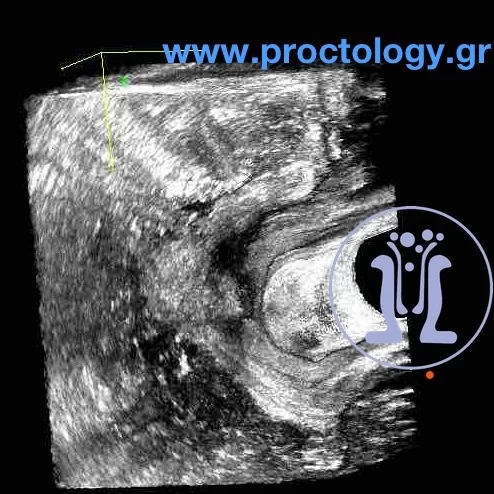

Περίπτωση ασθενούς με ακράτεια στα αέρια και συρίγγιο μετά από εγχείρηση νεαροποίησης ραγάδας με laser. Φαίνεται σαφώς το στόμιο του συριγγίου και στο ενδοπρωκτικό υπερηχογράφημα … Περισσότερα

Περιεδρικό συρίγγιο με ακράτεια στα αέρια σαν επιπλοκή νεαροποίησης ραγάδας με laser. Οπίσθια έσω σφιγκτηροτομή ολικού μήκους- keyhole deformity